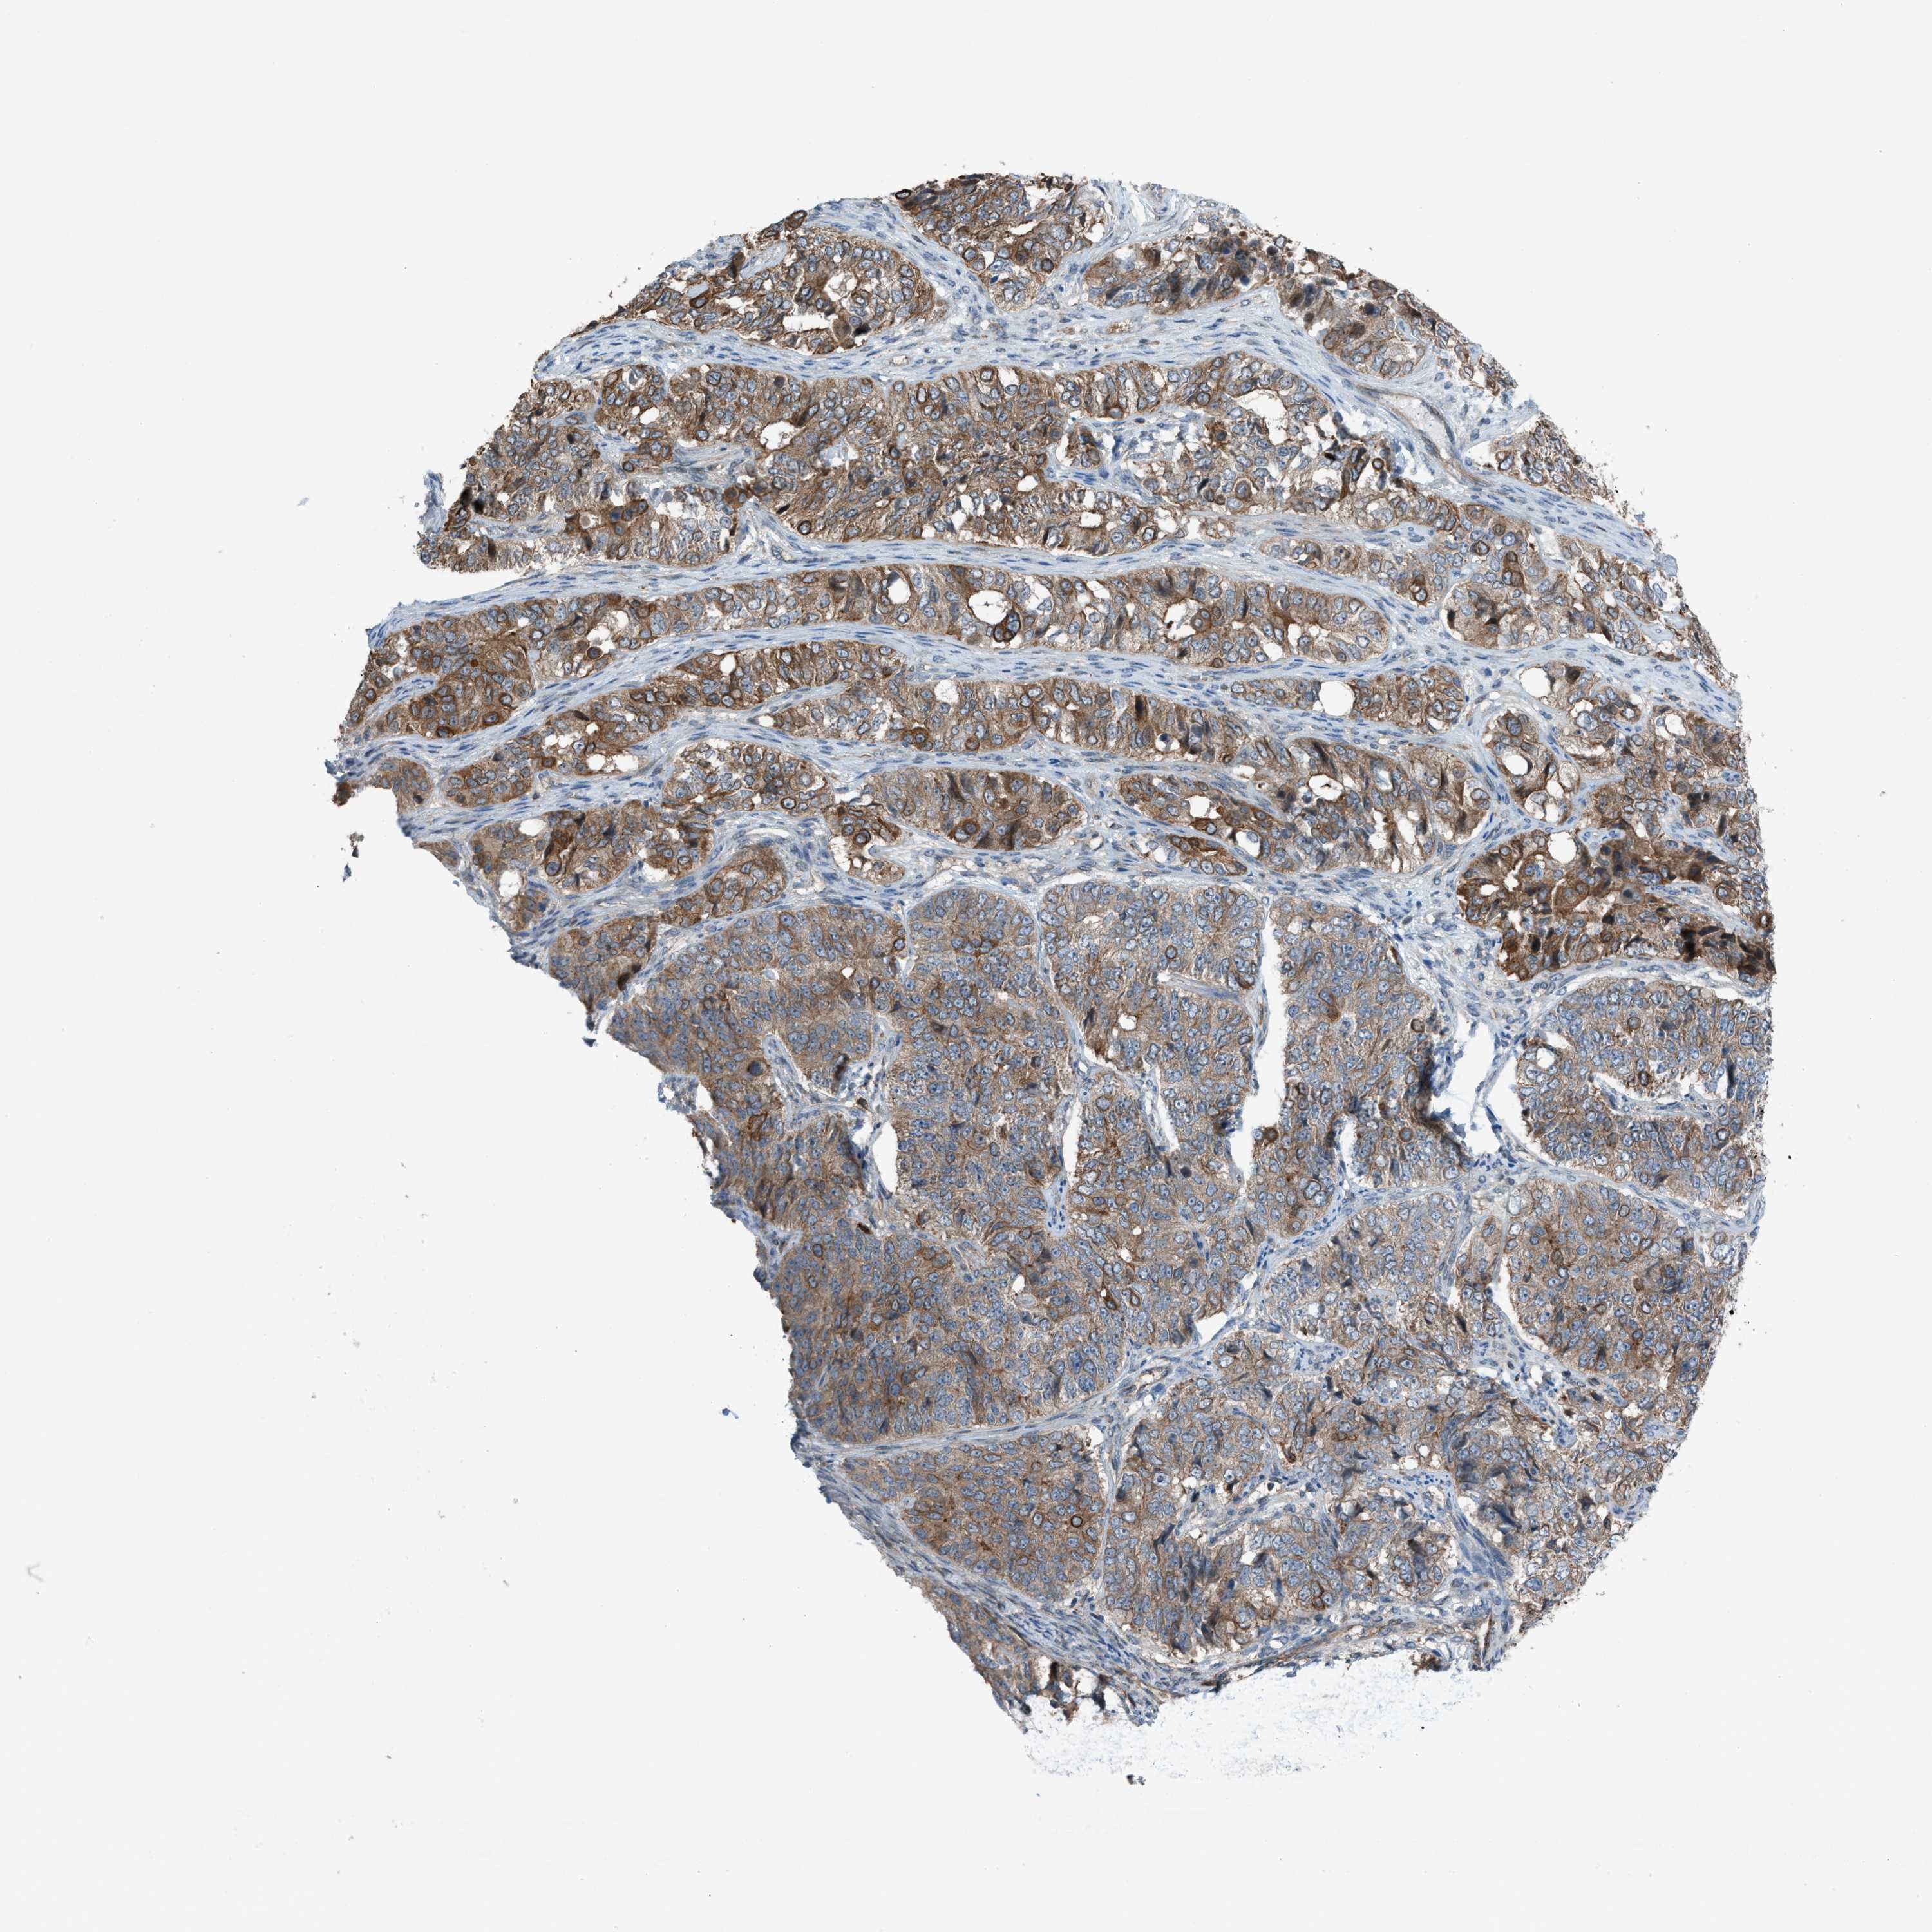

OVARIAN CANCER - Protein expressioni

A mouse-over function shows sample information and annotation data. Click on an image to view it in a full screen mode. Samples can be filtered based on level of antibody staining by selecting one or several of the following categories: high, medium, low and not detected. The assay and annotation is described here.

Note that samples used for immunohistochemistry by the Human Protein Atlas do not correspond to samples in the TCGA dataset.

Antibody stainingi

Antibody staining in the annotated cell types in the current human tissue is reported as not detected, low, medium, or high, based on conventional immunohistochemistry profiling in selected tissues. This score is based on the combination of the staining intensity and fraction of stained cells.

Each image is clickable and will lead to virtual microscopy that enables deeper exploration of all samples and also displays staining intensity scores, fraction scores and subcellular localization as well as patient and tissue information for each sample.

Antibody HPA015323

Antibody HPA015810

Cystadenocarcinoma, serous, NOS

Cystadenocarcinoma, mucinous, NOS